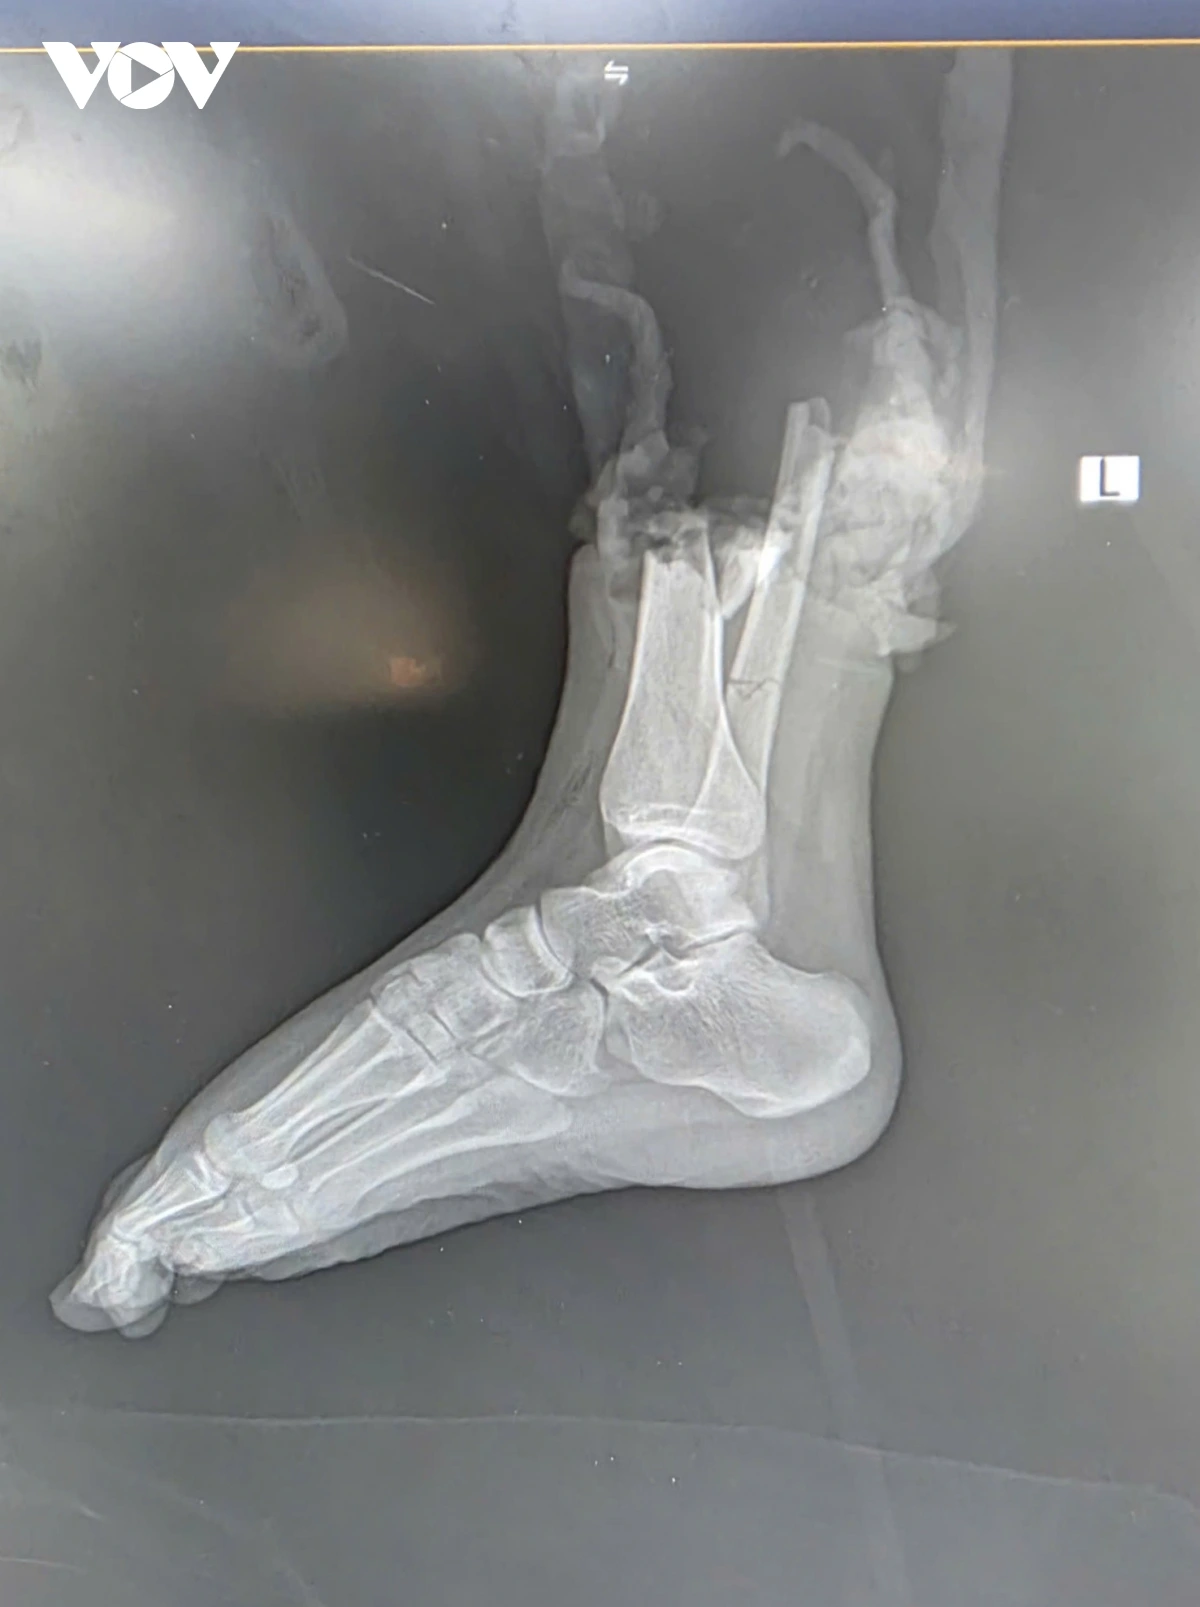

Thời điểm xảy ra vụ việc, một người đàn ông điều khiển mô tô phân khối lớn di chuyển với tốc độ cao đã va chạm mạnh với xe máy Honda Wave Alpha chở hai người. Cú đâm khiến hai người trên xe máy bị thương nặng, trong đó chị Đ.P (19 tuổi, quê Bắc Ninh), người điều khiển xe máy bị đứt lìa ở ví trí phức tạp, 1/3 dưới cẳng chân phải, kèm dập nát phần mềm.

Ngay sau tai nạn, chị Đ.P được sơ cứu và nhanh chóng chuyển tới Bệnh viện Trung ương Quân đội 108 trong “thời gian vàng” - khoảng 2 giờ sau chấn thương. Trong đêm khuya, kíp y bác sĩ đã nhanh chóng tiến hành cắt lọc, xử lý tổn thương, nối mạch máu, thần kinh, gân cơ và xương. Sau hơn 6 giờ phẫu thuật căng thẳng, phần chi thể đứt rời được trồng nối thành công. Sau phẫu thuật gần 2 tuần, bệnh nhân đã khỏe mạnh và có thể cử động được các ngón chân, cho thấy kết quả phục hồi khả quan.